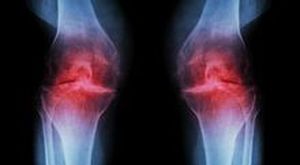

Самыми распространенными патологическими состояниями, при которых болят коленки, являются воспалительные процессы. Они носят название артритов, сопровождаются повышением температуры в области сустава, припухлостью, деформацией. При отсутствии лечения и воздействия на причину заболевания процесс имеет склонность к прогрессированию и ухудшению состояния. В конечном итоге у больного развивается инвалидность. Бывает несколько разновидностей данного заболевания:

- Ревматоидный артрит. Относится к самым распространенным болезням суставов аутоиммунного происхождения. Поражает симметрично преимущественно мелкие суставы, но иногда возникает и в колене. Характерным симптомом является скованность в утреннее время (степень ее выраженности считается показателем активности процесса) и симметричность поражения, когда болят коленки как правая, так и левая. Она сопровождается болью в области пораженного сустава, усиливающейся при длительном сидении.